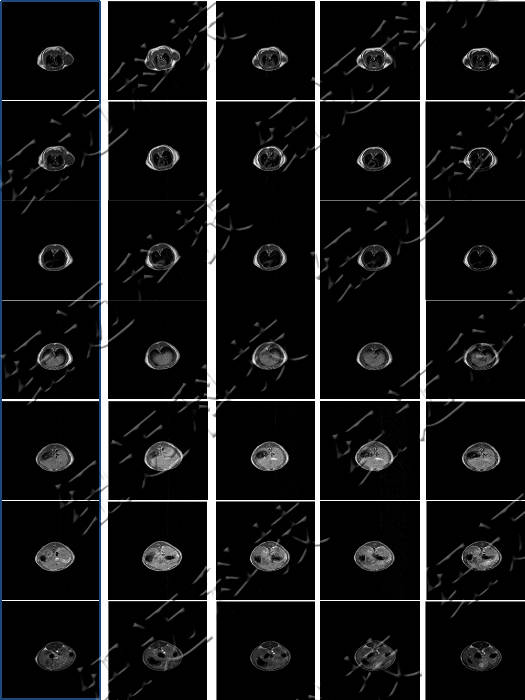

根据不同磁性物质主要作用于Tl或T2加权造影成像,造影剂同样分为Tl造影剂或T2造影剂。国外造影剂的研究十分活跃,已有多种造影剂投入生产并进入了临床应用。目前已经被食品药品监督管理局批准上市的基于钆配合物的造影剂有7种。

测试钆类MRI造影剂弛豫率测试以及造影剂样品的T1加权成像。

弛豫效率是MRI造影剂关键指标之一。

造影剂:通过内外界弛豫效应和磁化率效应间接地改变组织信号的强度,以增加组织或器官对比度的一类物质。

核磁共振成像(MRI)目前普遍应用于医学检测成像中,具有无辐射损伤的安全性,可任意方位断层扫描等技术灵活性,加以涵盖质子密度、弛豫、加权成像以及多参数特征的优势,已成为当代临床诊断中最有力的检测手段之一,然而临床发现某些不同组织或肿瘤组织的弛豫时间相互重叠,导致诊断困难。